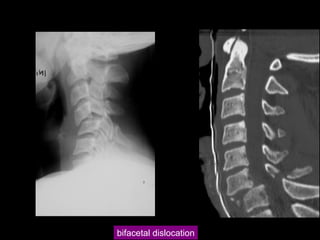

unifacetal dislocation

bifacetal dislocation